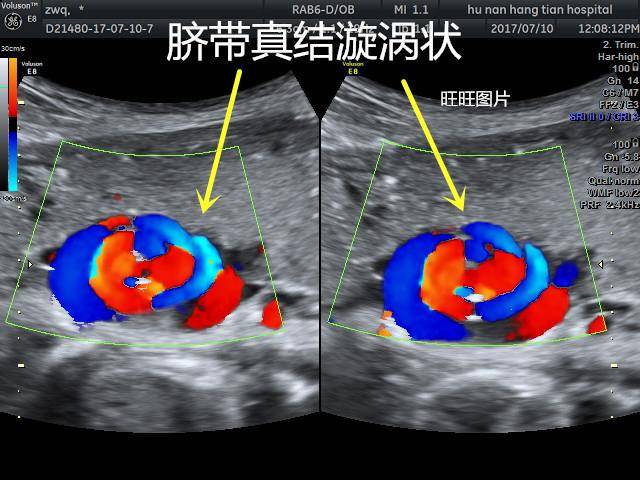

脐带打结